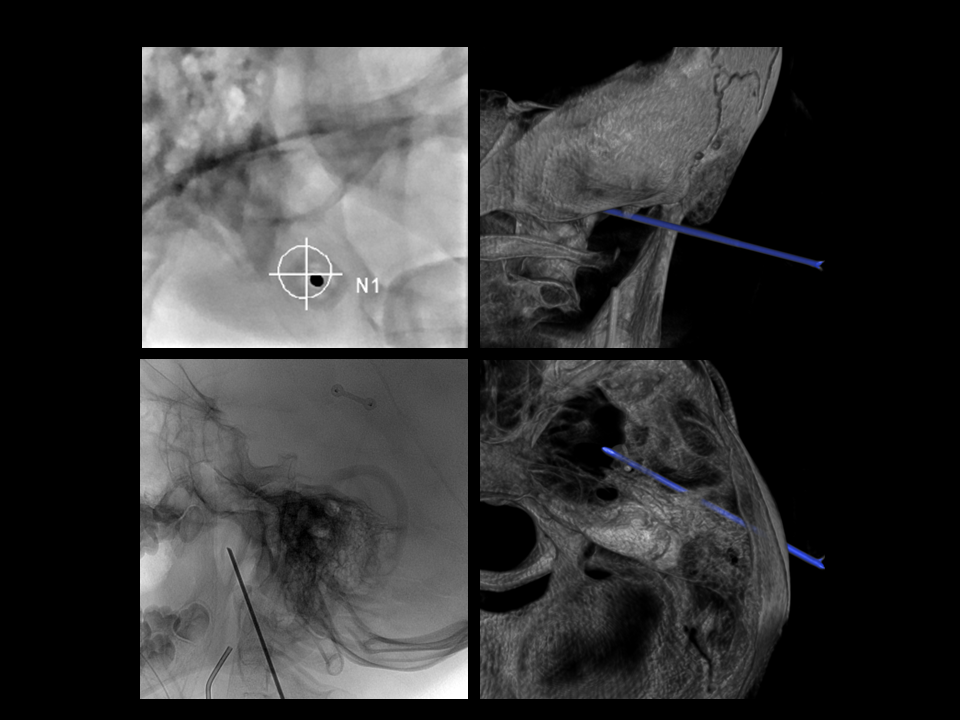

CSF Lymphatic Fistula

A fantastic and unique case